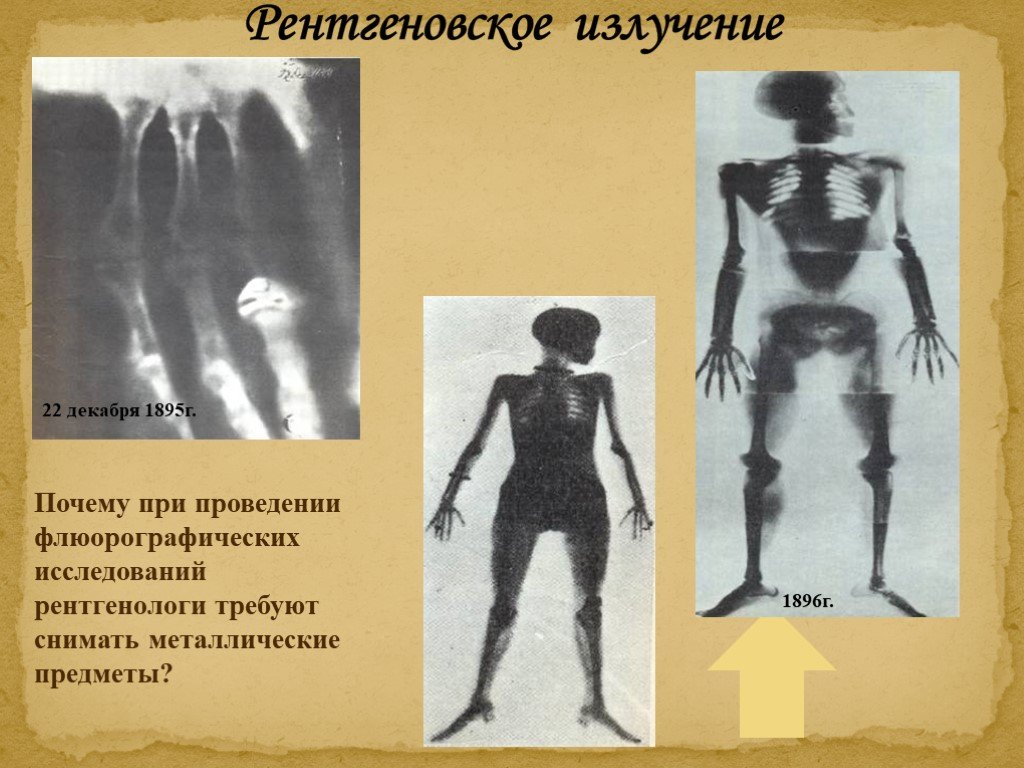

Изучение дозы излучения при рентгеновских исследованиях: визуализация

Раздел: Фотодневник открытий